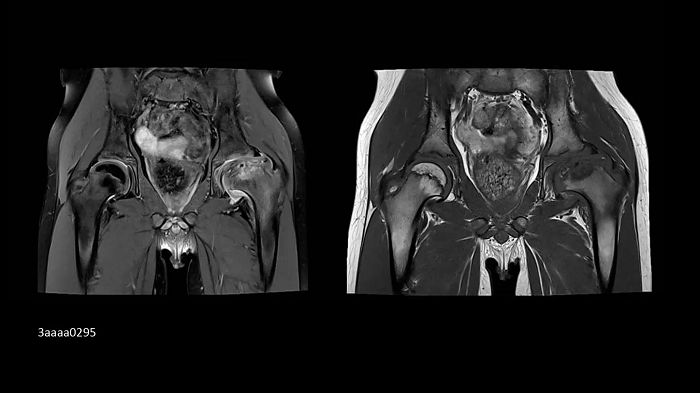

Orthopedics

Hip imaging with the new Ultraflex Coils

In pediatrics, high-resolution bilateral hip imaging with the new UltraFlex Coils was performed on an 8-year-old boy.

Image Credit: Radiologie Miinchen Harlaching, Munich, Germany